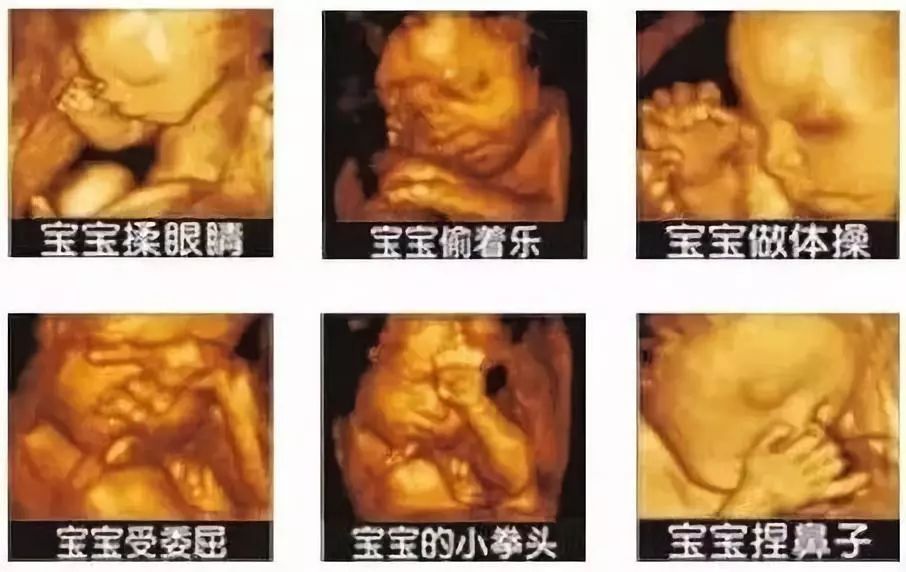

记录宝宝的每一个成长瞬间是所有父母的心愿,有一些商家瞅准了这个商机,推出用超声技术为宝宝拍照留念。是不是看起来萌萌哒?有那么一些心动?

准爸妈们爱宝宝的心情可以理解,但并不建议这样做。虽然目前超声是公认安全的影像学检查手段,没有明确可靠的证据证明现在使用的超声诊断会对胎儿造成伤害,但也不能证明超声能量对于胎儿完全无害。

我国规定胎儿超声检查应遵循“最小剂量原则”,国际妇产科超声学会及世界超声医学生物*联学**盟提出,孕期超声检查需要有明确的医学检查指征,不赞成纯粹为了提供胎儿纪念相片而进行的超声。美国食品药物协会也提出推广、销售、租用超声仪器去做胎儿纪念视频是不合法的。为了减少对宝宝未知的伤害,建议孕妈们不要为还未出世的宝宝随便“拍照”。